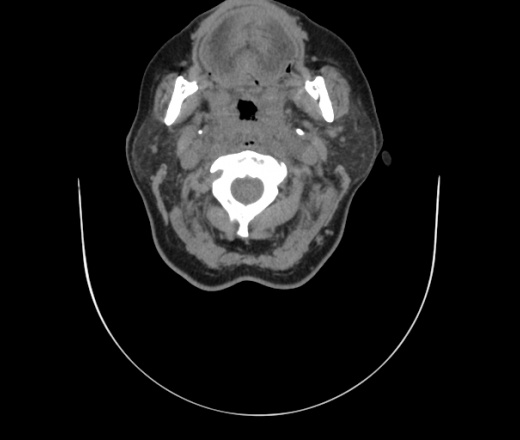

Женщина поступила в х/о спустя 4 дня после того как при употреблении карася подавилась костью.

Наличие газа в средостении на протяжении тел С2-С6 (медиастинальна эмфизема); рыбная кость на уровне тела С6.

При всем уважении, но говорить о медиастинальной эмфиземе, оценивая мягкие ткани шеи, как-то слишком резко. На мой взгляд, это ретрофарингеальное пространство.

Согласен с Вами; конечно, наличие газа в клетчатке ретрофарингеального пространства (затмение с опечаткой..). К сожалению, процесс "продвигается" к медиастиниту. Но почему никто, не отмечает наличие рыб. кости; или это для Всех очевидно?

Кость то мы сразу выявили, размеры где то 17*2мм, но ее так и не получается найти в этой каше